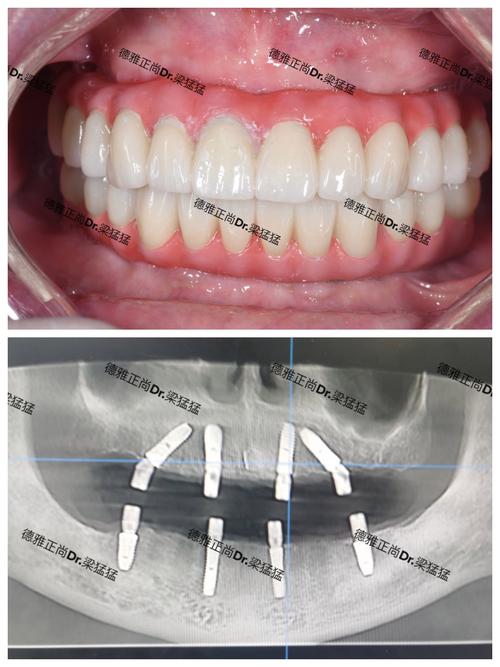

- 原理: 将一个纯钛的种植体(人工牙根)通过小手术植入到缺牙位置的牙槽骨内,等种植体与牙槽骨紧密结合(骨结合)后,在种植体上安装基台,再在基台上安装牙冠(可以是全瓷冠)。

- 美观自然: 配合全瓷牙冠,美观效果非常好,几乎可以乱真。

- 从长远健康、功能 preservation(保存邻牙和骨组织)、咀嚼效率和成功率来看,种植牙通常是修复牙齿缺失的“金标准”和首选方案。 尤其是对于单颗缺牙、后牙缺牙、多颗缺牙以及全口缺牙。